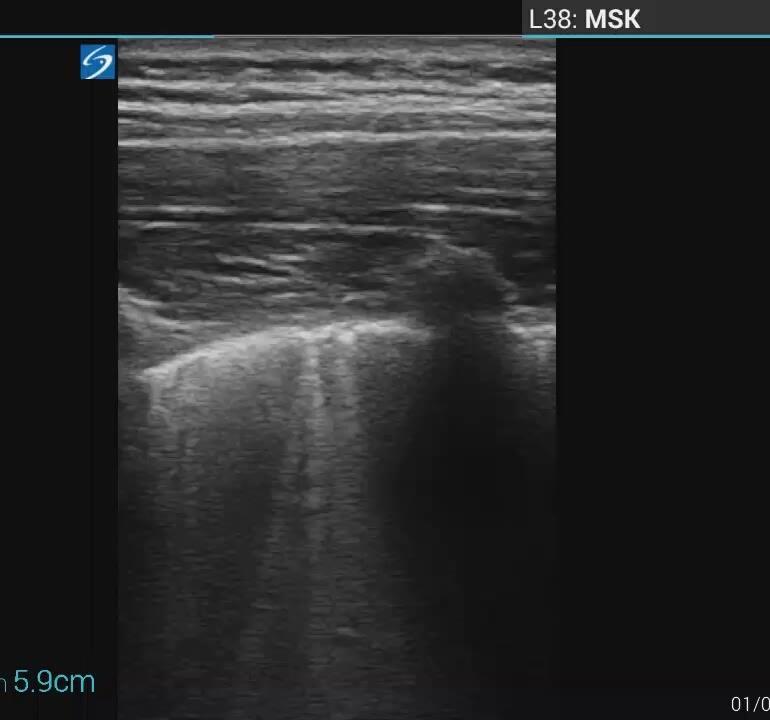

Pediatric COVID-19: MIS-C

Thoracic abnormalities

Cardiovascular abnormalities

Cardiomegaly

CHF or cardiogenic edema

Pulmonary parenchymal abnormalities

Lower lobe atelectasis

Bilateral opacities( ARDS)

Consolidation

Pleural abnormalities

Small pleural effusion

Mediastinal and hilar lymphadenopathy

Abdominal abnormalities

Solid viscera abnormalities

Hepatomegaly

Echogenic kidneys

Splenomegaly

Hollow viscera abnormalities

Gallbladder wall thickening

Bowel wall thickening

Bowel dilation

Gastric distention

Urinary bladder thickening

Peritoneal abnormalities

Small ascites

Mesenteric abnormalities

Mesenteric lymphadenopathy